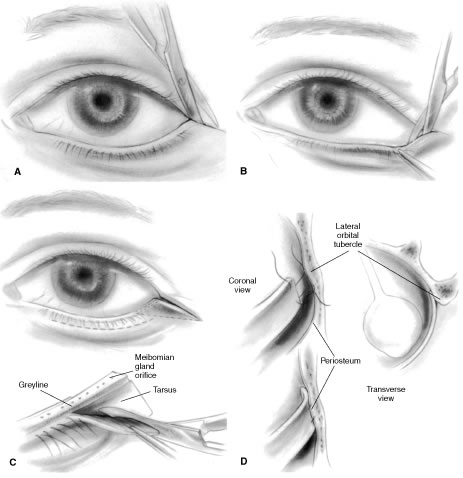

Thorough knowledge of eyelid anatomy is essential for the appreciation of the etiology and surgical intervention of lower eyelid abnormalities. The eyelid can be conceptionalized to consist of an anterior and posterior lamella. The anterior lamella consists of the skin and orbicularis muscle. The thin delicate skin of the eyelid lacks the connective tissue, fat, and pilosebaceous apparatus of the dermis that would reduce eyelid mobility. The orbicularis muscle is categorized as either orbital or palpebral portions based on its association with adjacent anatomic structures. The orbital orbicularis muscle overlies the orbital rim. The palpebral orbicularis muscle is further classified as preseptal or pretarsal based on the proximity of orbital septum or tarsus, respectively. At the eyelid margin a strip of orbicularis muscle, the muscle of Riolan, is directly associated with the eyelashes. This is responsible for the darker coloration of the slightly depressed midsection of the lid margin commonly referred to as the gray line.1

The posterior lamella consists of the eyelid retractor, the tarsus, and the conjunctiva. Hawes and Dortzbach2 reviewed and highlighted lower eyelid anatomy, specifically the lower eyelid retractor (Fig. 1). The lower eyelid is analogous to the upper eyelid; the main variation is the eyelid retractor system. The upper eyelid has a distinct eyelid retractor, the levator muscle, to enhance upper eyelid mobility. The lower eyelid does not have a specialized eyelid retractor. The lower eyelid retractor system originates as a fascial extension of the inferior rectus muscle (capsulopalpebral head). This fascial system splits to encapsulate the inferior oblique muscle and then reunites to form a dense fibrous sheet (capsulopalpebral fascia) to insert onto the inferior tarsal border. The inferior tarsal muscle is a smooth muscle analogous to the superior tarsal muscle (Müller's muscle) of the upper eyelid. This muscle originates in the inferior fornical area and extends toward the inferior tarsal border but does not insert on the tarsal border as its counterpart in the upper eyelid does. The inferior tarsal muscle receives sympathetic innervation, and interruption of its innervation will result in a slightly elevated position of the lower eyelid margin as observed in Horner's syndrome. Otherwise, the inferior tarsal muscle has little pathologic significance.

The tarsus provides the primary support or foundation for the eyelids. Although degeneration of the tarsus may promote eyelid laxity,3 the principle focus of weakness of the eyelids is at the lateral and medial canthal tendons.4 Jones and Wobig5 described the medial canthal tendon with a prominent anterior component firmly connecting the medial canthal angle to the maxillary process of the frontal bone. The posterior limb of the medial canthal tendon provides deep support to the posterior lacrimal crest. Anderson6 also emphasized the role of a superior branch of the medial canthal tendon to support the canthal angle. Gioia and coworkers7 have provided a clear description of lateral canthal anatomy. The lateral canthal tendon has contributions from the lateral aspects of the tarsus and the preseptal and pretarsal orbicularis muscle; these insert on the inner aspect of the lateral orbital rim at Whitnall's (lateral orbital) tubercle. The posterior deep insertion of the lateral canthal tendon allows the lateral aspect of the eyelids to approximate the globe.